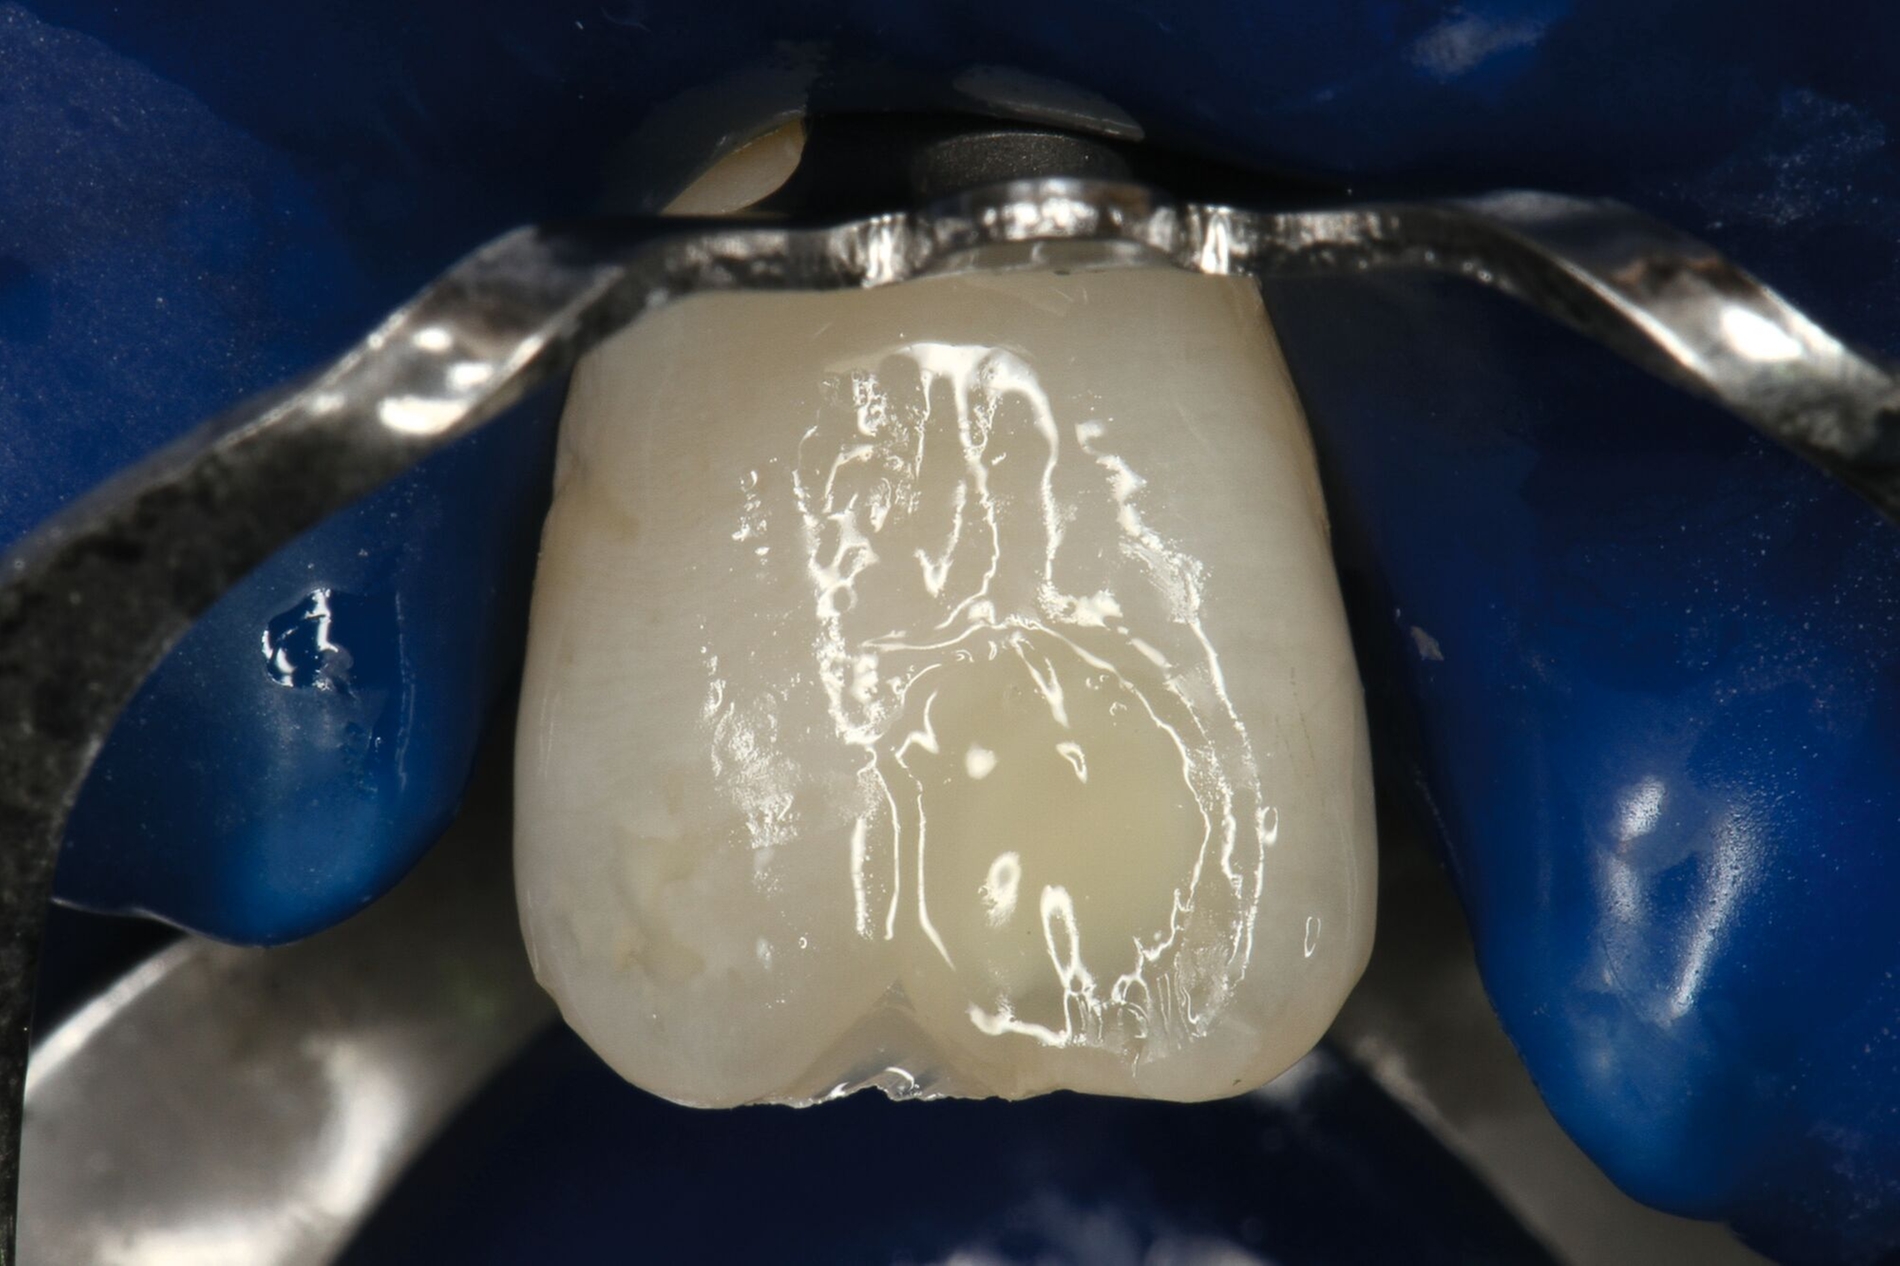

Vor der adhäsiven Befestigung sollten sowohl das Fragment wie auch der Zahn gründlich gereinigt werden. Sandstrahlen kann eine gute Option sein, um Reste von provisorischem Material zu entfernen, die während der Notfallbehandlung zur Versiegelung des Dentins aufgebracht wurden. In Bereichen mit reduzierter Restdentinstärke ist jedoch höchste Vorsicht geboten, um keine Pulpaexposition zu riskieren. Zusätzliche Präparationen wie das Abschrägen der Schmelzränder oder das Präparieren einer inneren Rille im Dentin führen zu einer verbesserten Haftung, erschweren jedoch die exakte Repositionierung des Fragments. Dennoch kann im Einzelfall, bei offensichtlichen kohäsiven Schmelzrissen im Randbereich (aufgelockerte Schmelzprismen), eine vorsichtige Randpräparation sinnvoll sein, um eine qualitativ hochwertige Adhäsivfläche zu erzielen.

Zahnoberfläche und Fragment werden mit einem Adhäsivsystem vorbehandelt, wobei eine vorherige Schmelzätzung mit Phosphorsäure unabhängig vom verwendeten Adhäsivsystem sehr zu empfehlen ist. Bei gefüllten, schichtbildenden Adhäsivsystemen würde die Polymerisation des Adhäsivs die Passung des Fragments beeinträchtigen und sollte daher unterbleiben. Universaladhäsive sind diesbezüglich im Vorteil, da sie so dünn verblasen werden, dass sich trotz Vorhärtung keine Passungsprobleme ergeben. Ein fließfähiges Komposit wird auf die Bruchflächen beider Teile aufgetragen und über die Oberfläche verteilt. Nach der Reposition des Fragments wird überschüssiges Material entfernt und die Frakturlinie von labial und palatinal lichtgehärtet. Empfohlen werden leistungsfähige Polymerisationslampen und längere Belichtungszeiten, um sicherzustellen, dass über die Zahnstruktur genügend Energie an die gesamte Klebefläche abgegeben wird. Das Kühlen des Zahnes mit Druckluft hilft, den Temperaturanstieg während der Polymerisation zu verringern und kann somit hitzebedingten Pulpaschäden vorbeugen. Kompositüberschüsse, die nach der Polymerisation im Bereich der Frakturlinie verbleiben, können einfach mit einem Skalpell entfernt und bei Bedarf poliert werden. Im Einzelfall kann bei einer geringen Klebefläche die Frakturlinie nach der adhäsiven Wiederbefestigung hohlkehlartig ausgeschliffen und anschließend mit Komposit aufgefüllt werden.